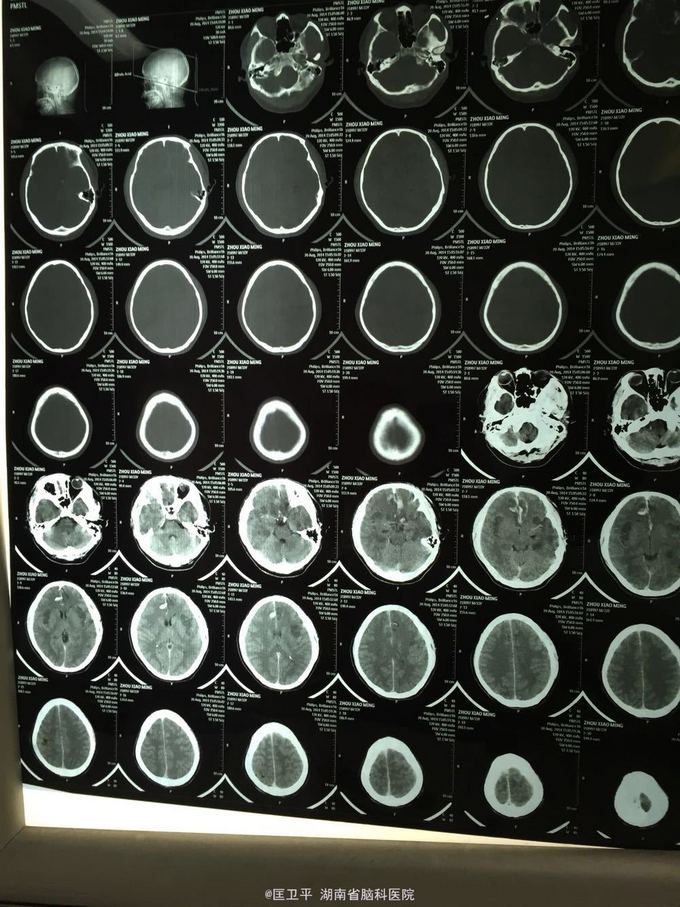

电击伤后智力低下,伤人毁物1年。 一年前在工地被电击伤昏迷,心跳呼吸停止,十几分钟后才有不规范的人工呼吸,持续约40分钟,心跳呼吸恢复。但患者智力低下,远近记忆很差,疑人害,伤人毁物严重,无法管理。

神清欠合作,五官无畸形,四肢活动正常,无神经定位体征。智能记忆很差,有被害妄想,有冲动攻击行为,无自知力,个人生活无法自理。